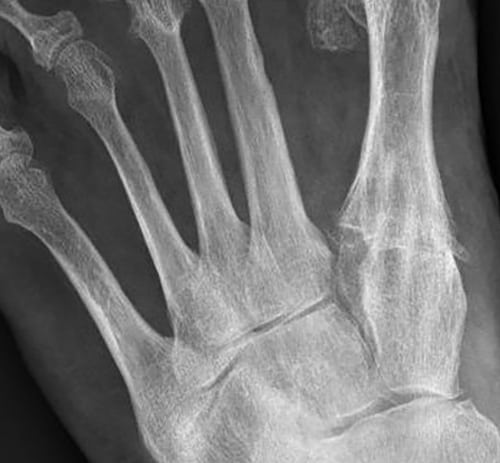

X-ray image preoperatively

Pronounced severe hallux valgus with metatarsus primus varus